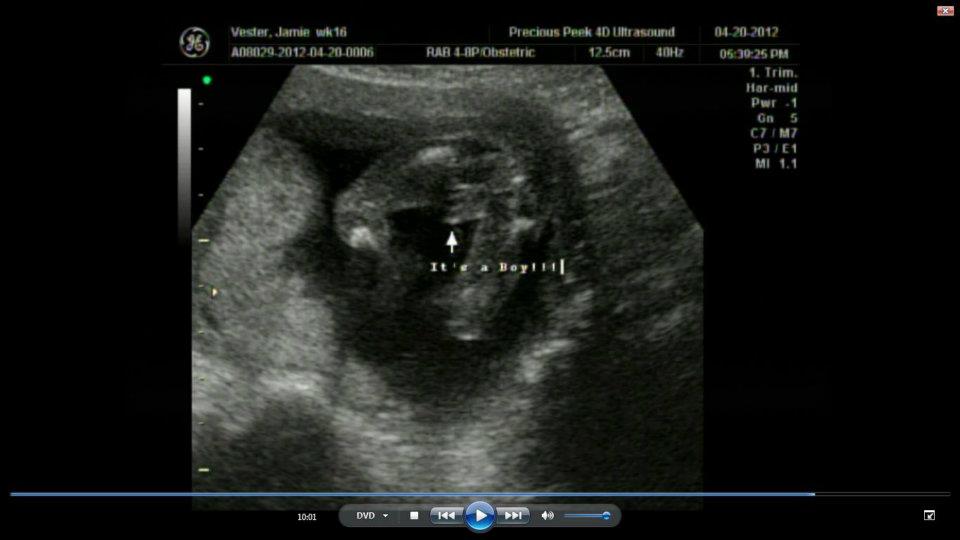

My pregnancy was a bit rough in the sense of I puked pretty much every single day but it was all worth it in the end! It is amazing to know that a baby is growing inside of you. A woman’s body is amazing. We can grow a child and feed a child once they are born – simply amazing. Have I said amazing yet? haha Around 20 weeks we found out that this miracle child of ours is a boy! Boy, oh boy! Time to start decorating the nursery and getting ready for this little guys arrival in September.